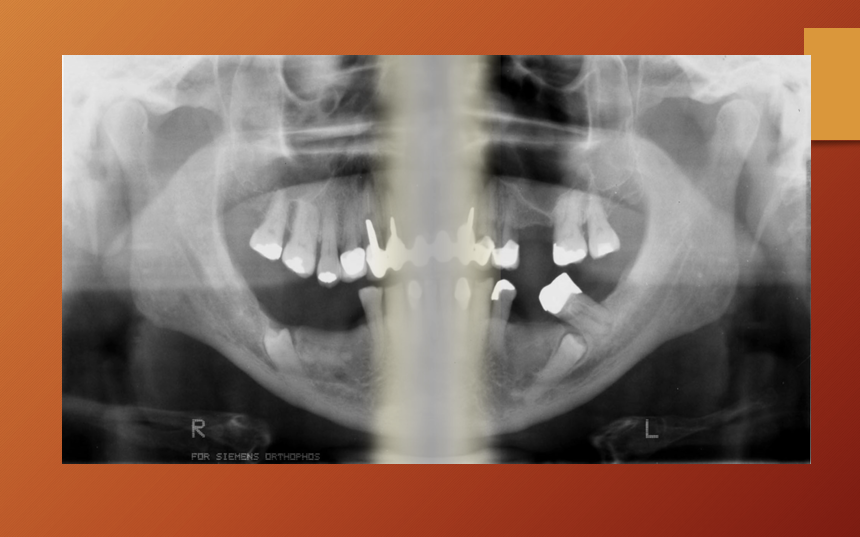

What id the age of this patient?

child